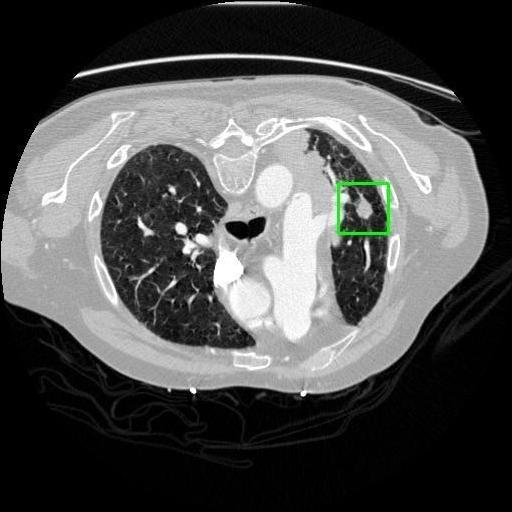

We developed an AI-based system using deep learning models for analyzing lung CT scans to detect and classify pulmonary nodules. We chose the YOLOv11 architecture for its enhanced object detection capability and adapted it specifically for medical imaging, incorporating pixel-level precision and severity classification.

Classification into three severity levels with colored bounding boxes.

Successfully built and deployed an AI model (YOLOv11) capable of detecting lung nodules in CT scans with high accuracy and real-time performance.

Designed a severity classification system that categorizes nodules into null, moderate, and severe using colored bounding boxes, assisting in rapid clinical decision-making.